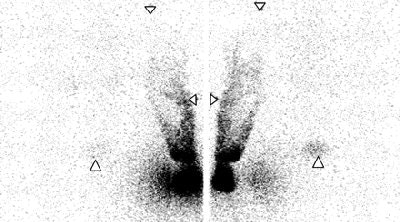

| Lymphoscintigraphy images of upper limb and torso in female patient. Downward-pointing arrowheads = shoulders, lateral arrowheads = elbows, upward-pointing arrowheads = pubic bone. Images obtained 52 and 48 minutes after intradermal (above) and subcutaneous (below) injections, respectively. There is greater clarity and earlier visualization of lymphatic structures after intradermal injection. Left and right panels are posterior and anterior images, respectively. |

"Lymphatic structures were visualized earlier and with unequivocally greater clarity after intradermal injection compared with subcutaneous injection in all six patients," the authors wrote. In addition, discrete lymphatic vessels in the upper arm were seen in five patients after intradermal injection.

No clear difference was seen between the two techniques with respect to activity outside the depot, they stated. However, arm activity steadily increased after subcutaneous injection, while after intradermal detection, arm activity reached a peak and then declined.